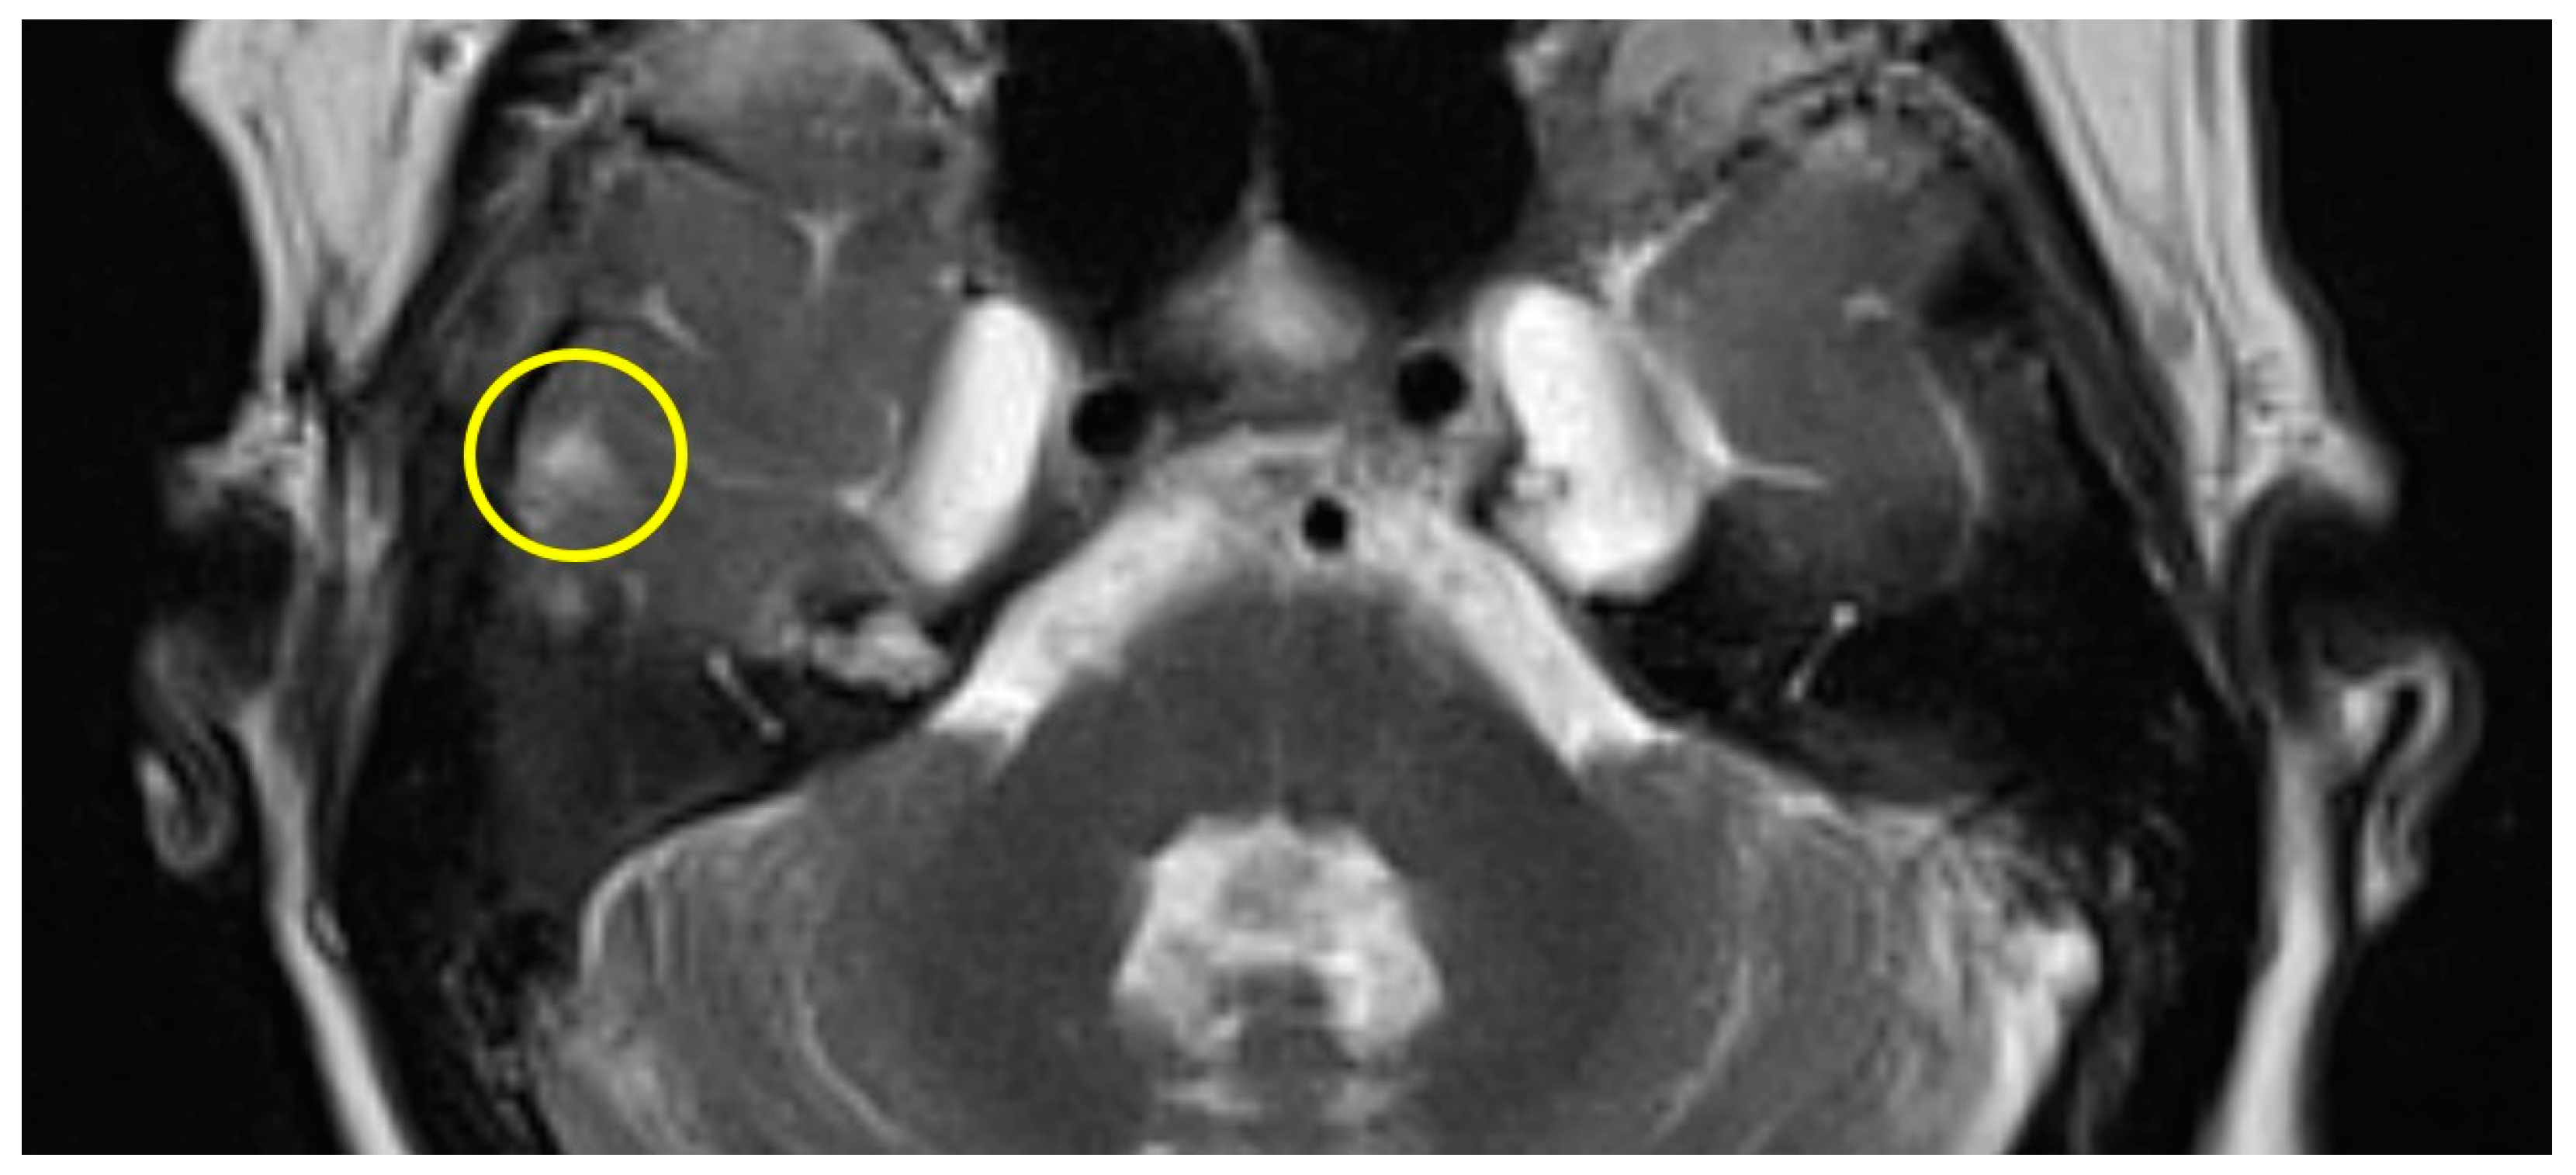

Patient #1 exhibited a slight gliosis on the left side during the follow-up MR 12 months postoperatively. On axial T2 weighted slides, a focal cortical and subcortical T2w signal increase was observed in the left temporal lobe (Figure 1). Patient #2 received early MR imaging only 3 months after surgery, which did not reveal any abnormalities. The subsequent second postoperative MR was conducted 16 months after surgery, revealing a slight gliosis of the right temporal lobe on the T2 axial images (Figure 2).

Figure 2.

Axial T2w MR imaging of patient #2 (yellow circle = gliosis). Supplementary MR imaging can be downloaded.